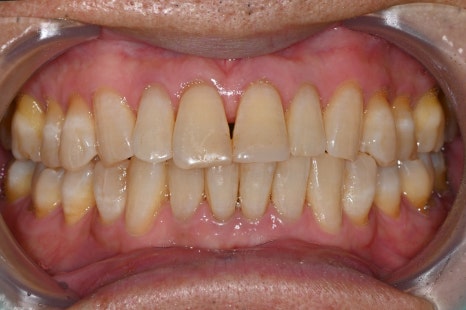

▼ 아래는 본원에서 치료한 실제 스케일링 전후 사진입니다.

-치료 전

왼쪽 사진: 병원에 첫 내원하셨을때 촬영한 구강 정면사진입니다.

- 치료 후

왼쪽 사진: 치석 제거 후 잇몸선이 깔끔하게 정리되며 구강 위생 개선 되었습니다.